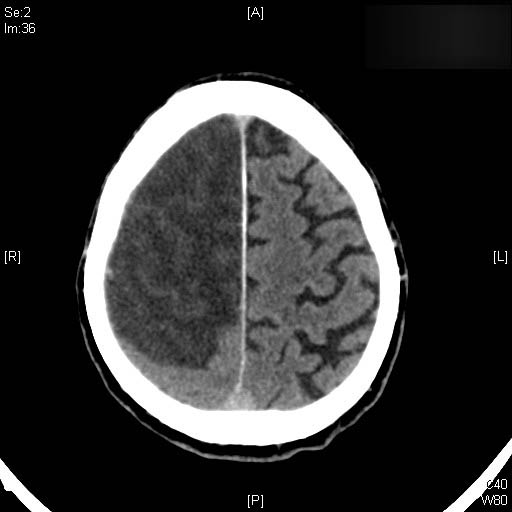

Hematoma subdural por caída.